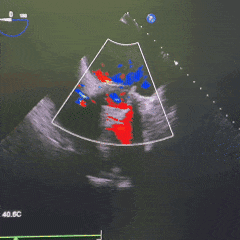

超声评估瓣膜位置可,无瓣周漏

术后超声

手术圆满成功,即刻效果显著!

-

峰值流速:2.90m/s→1.28m/s

峰值压差:34mmHg→8mmHg

瓣周未见明显反流